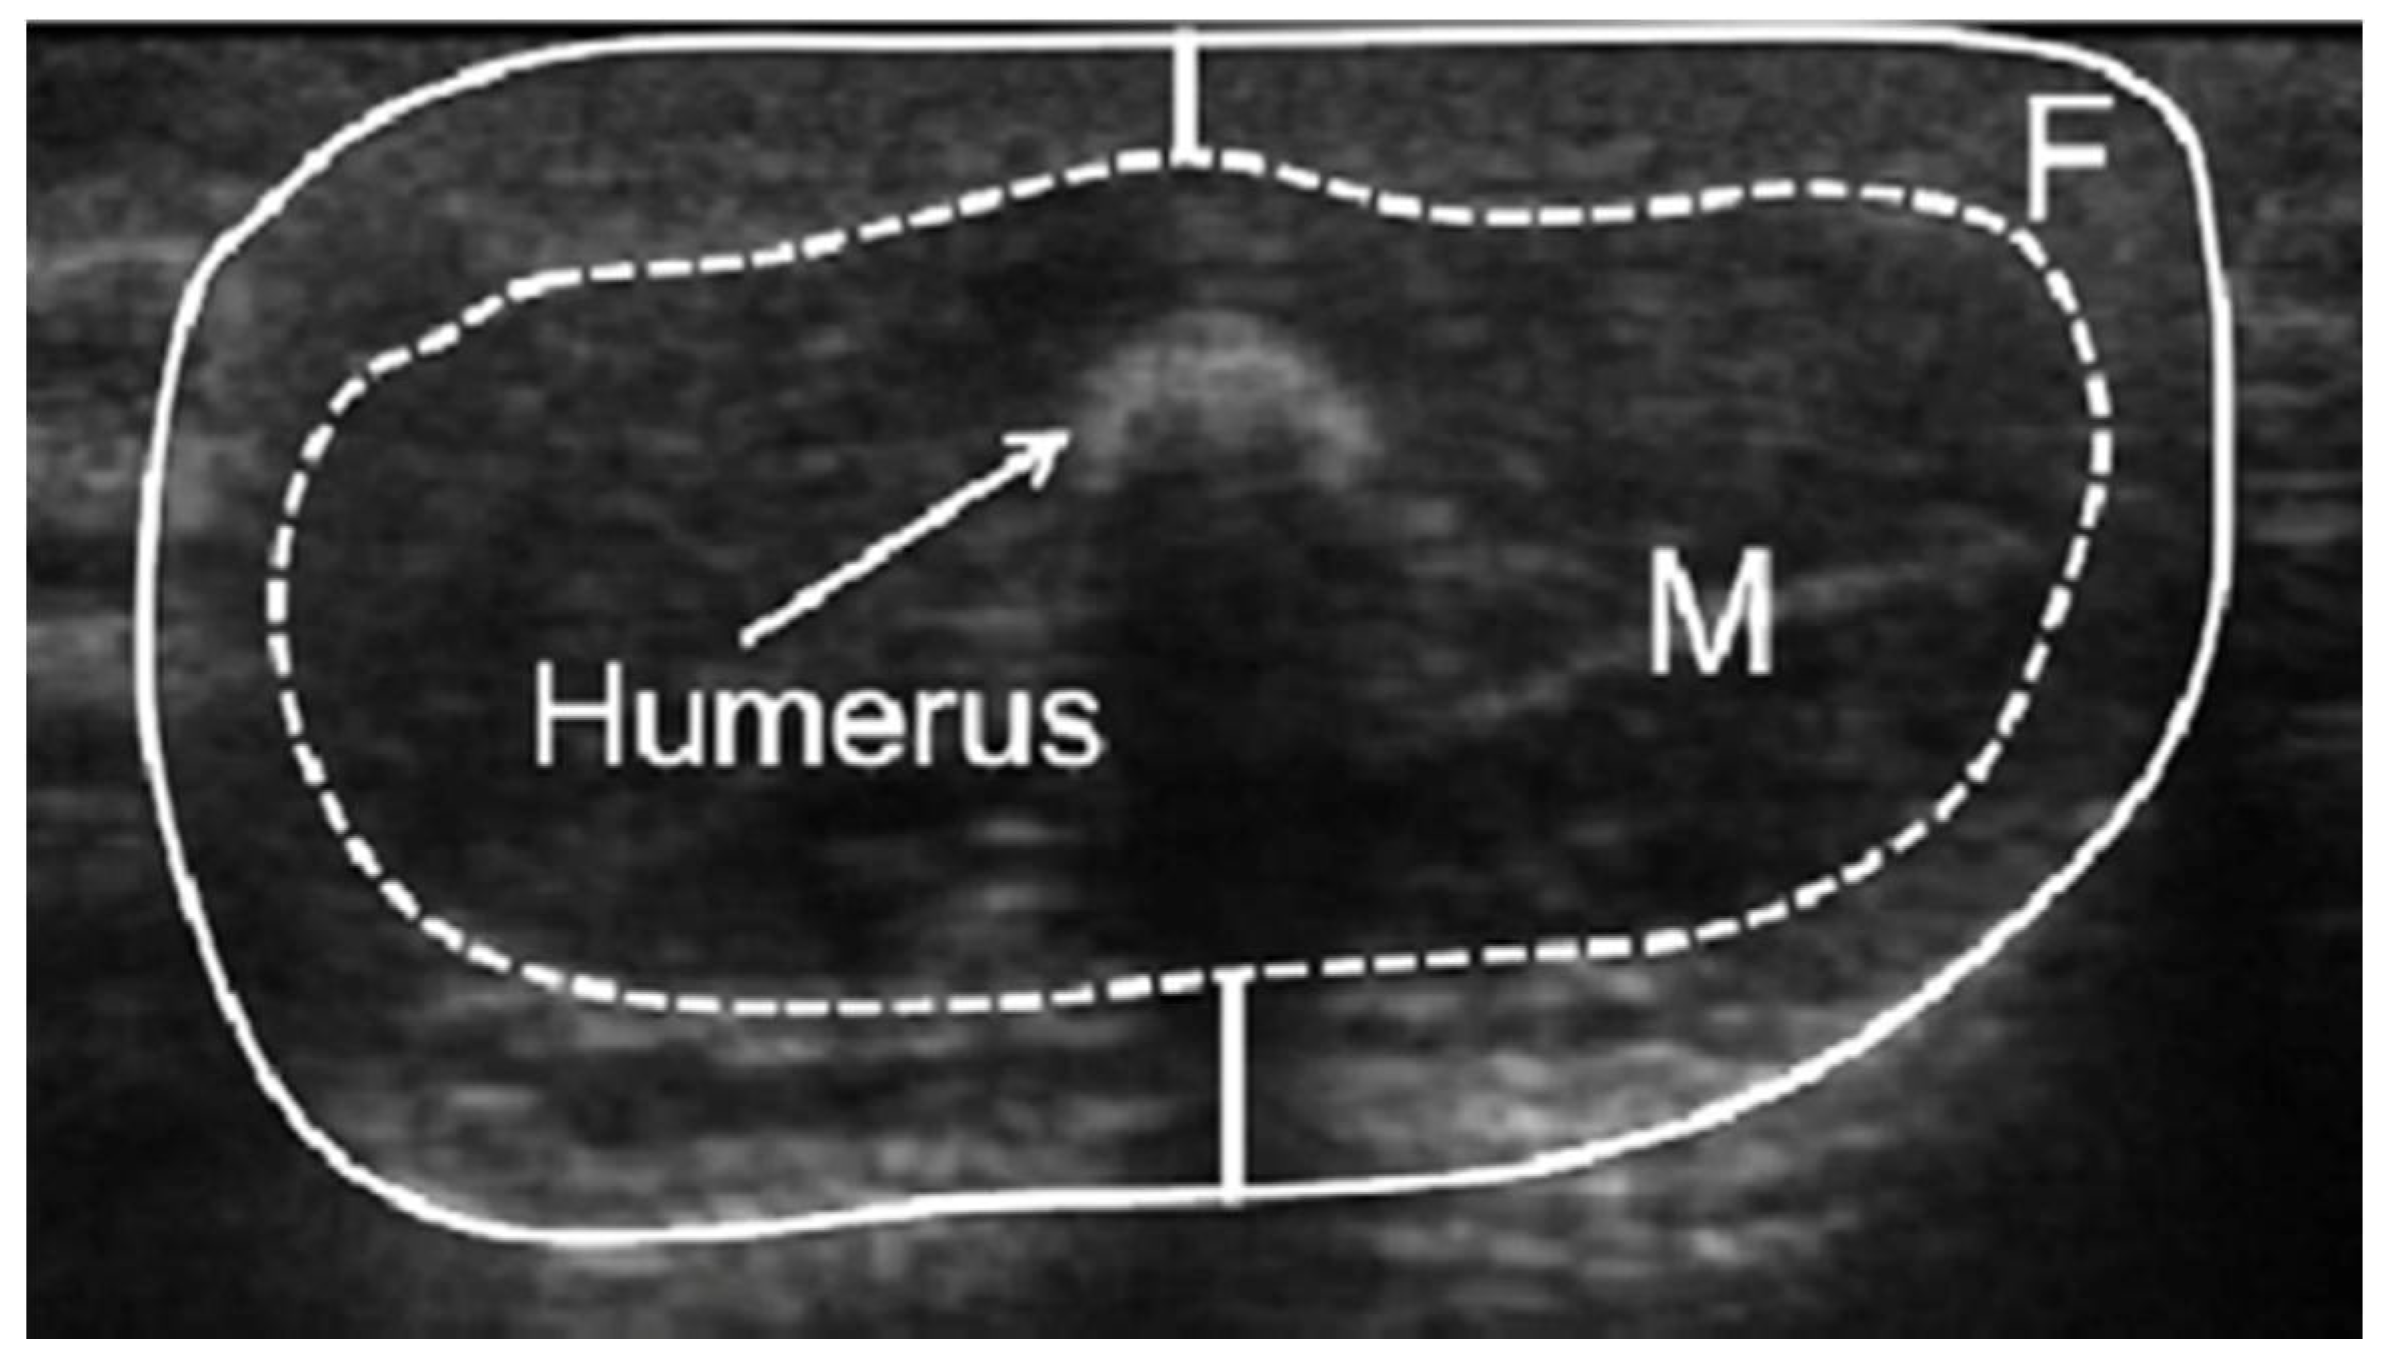

2.2. Measurements of Infant Limb Fat and Lean Areas

- McLeod, G.; Geddes, D.; Nathan, E.; Sherriff, J.; Simmer, K.; Hartmann, P. Feasibility of using ultrasound to measure preterm body composition and to assess macronutrient influences on tissue accretion rates. Early Hum. Dev. 2013, 89, 577–582. [Google Scholar] [CrossRef] [PubMed]